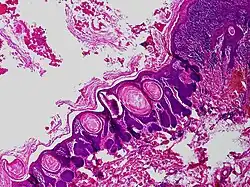

Trichofolliculoma is a cutaneous condition characterized by a benign, highly structured tumor of the pilosebaceous unit.[1][2] Trichofolliculoma is a rare tumor of the eyelid. It can be suspected by the “cotton bag sign”[3]